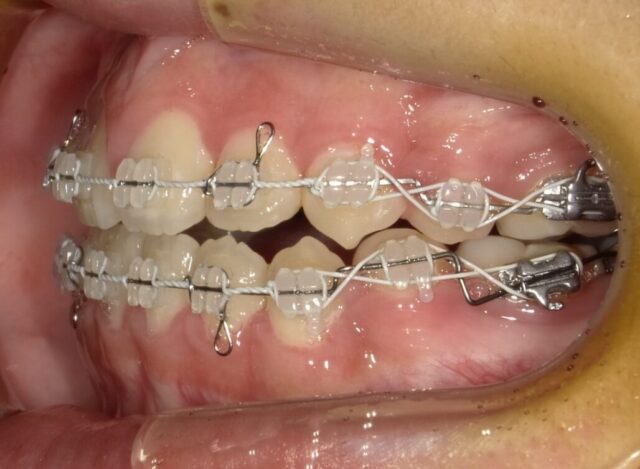

≪右側面観≫

2023年5月

2023年6月

2023年7月

2023年8月

2023年9月

2023年10月

2023年11月

2023年12月

2024年1月

2024年2月

2024年3月

2024年4月

2024年5月

2024年6月

2024年7月

2024年8月

2024年9月

2024年10月

2024年12月

2025年1月